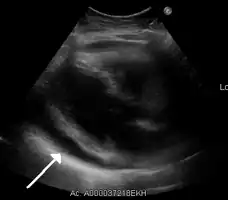

- Ultrasounds showing a pericardial effusion in someone with pericarditis

The diagnosis of tamponade can be confirmed with trans-thoracic echocardiography (TTE), which should show a large pericardial effusion and diastolic collapse of the right ventricle and right atrium. Chest X-ray usually shows an enlarged cardiac silhouette ("water bottle" appearance) and clear lungs. Pulmonary congestion is typically not seen because equalization of diastolic pressures constrains the pulmonary capillary wedge pressure to the intra-pericardial pressure (and all other diastolic pressures).